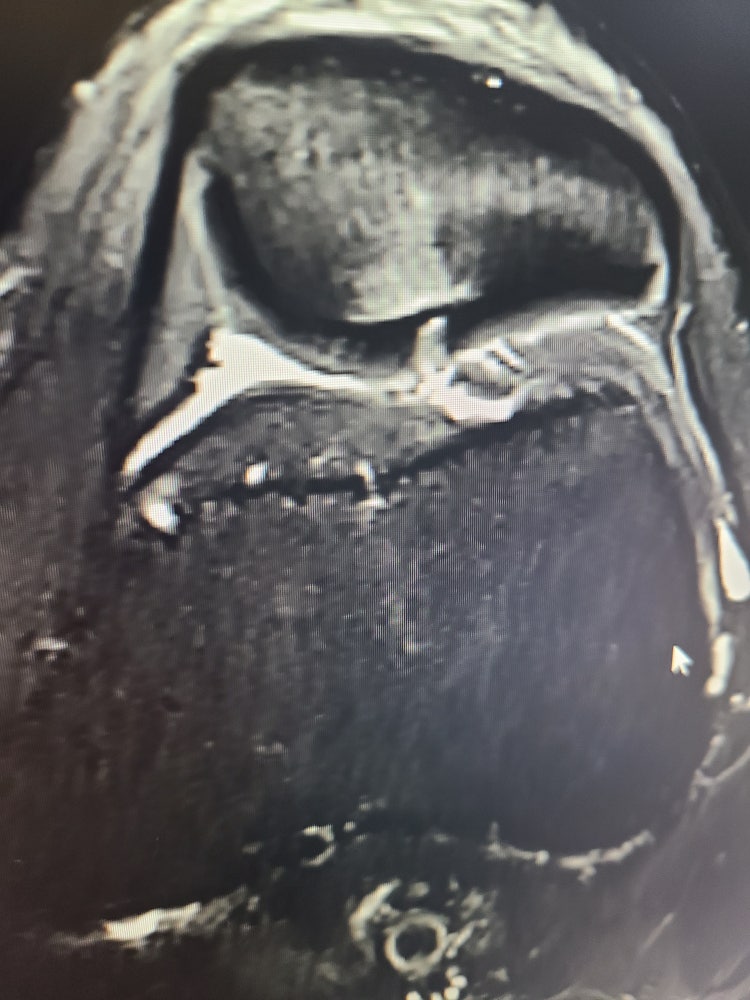

무릎.. 뭐가 조각났다, 뭐가낫다는데 수술필요성..

사진처럼 뾰족튀어나온거 때문에 통증있는거다.

뭐가 조각나서 돌아다니는거다.

계속 가만히두면 연골다친다...

혹시 판독이가능하실까요.

• 2번 째 사진

뼛조각이나 웃자란 뼈를 자르는 수술은 대부분 척추마취나 국소마취로 가능하기

때문에 경험이 충분한 정형외과 의사에게는 일반 병원에서도 문제가 되는 수술은

아닌 것으로 알고 있습니다.